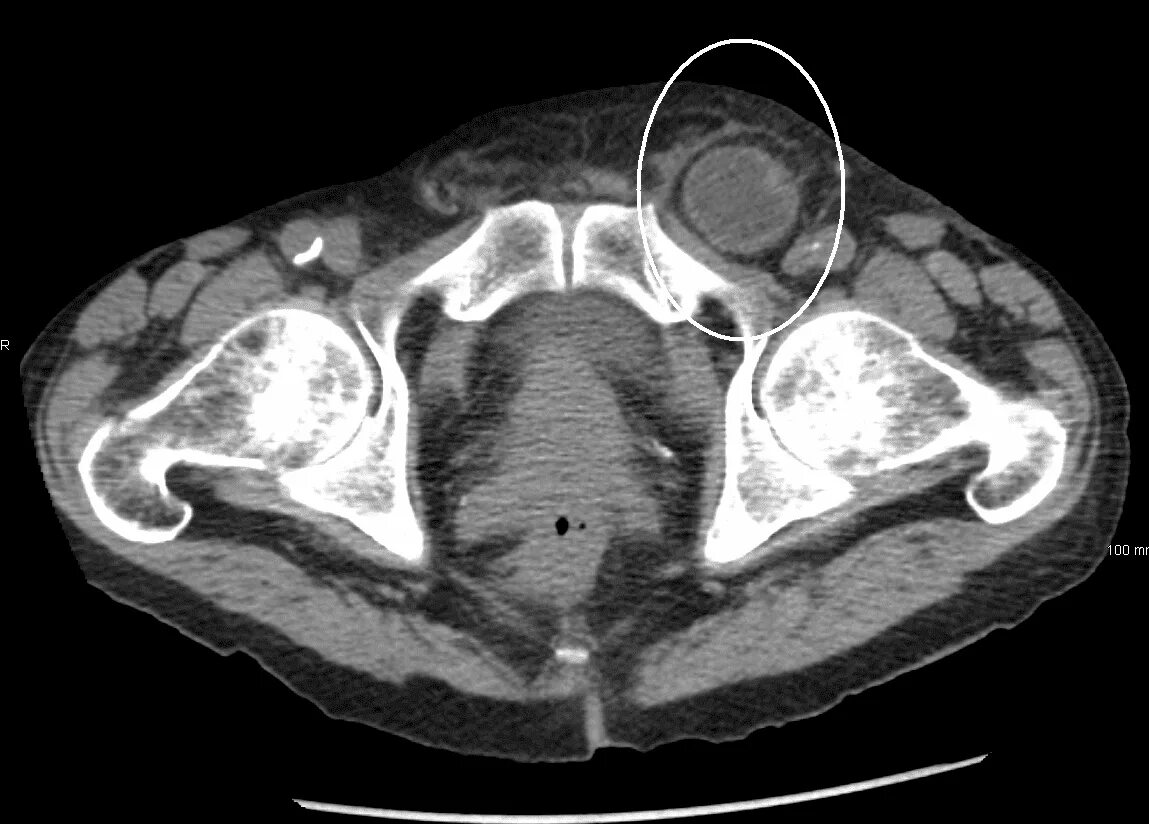

Грыжи на кт